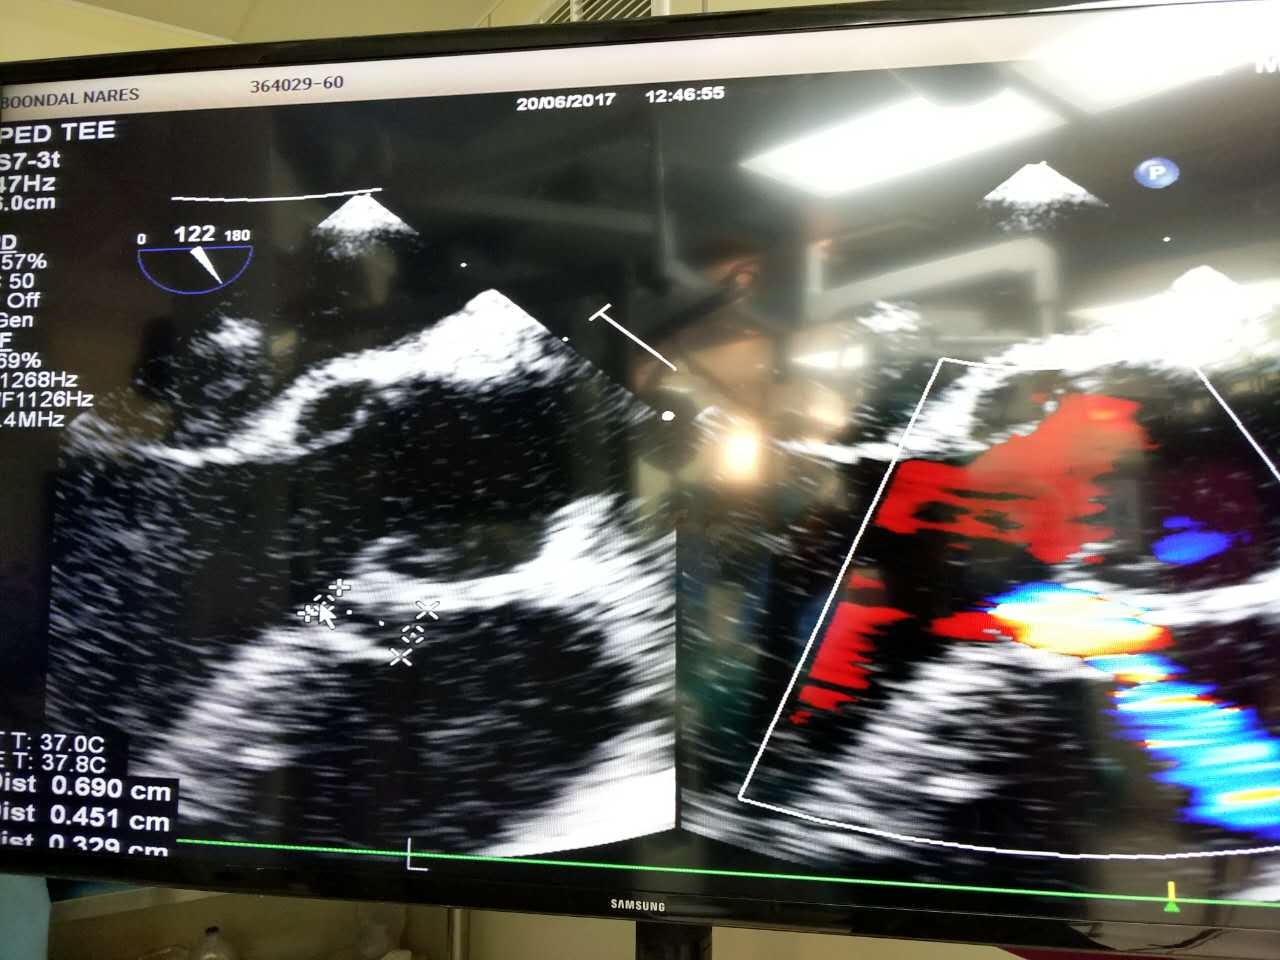

该患者被诊断为膜周部室距离缺损。术中丈量患者左室面缺损直径为4.5 mm,右室面缺损直径为3.3mm,缺损长度为6.9mm。该患者的室距离缺损地位位于自动脉瓣和肺动脉瓣的正下方,是临床上较为罕见的极具挑战性的病例,选取通常的封堵器极度难达到预期的手术成效。KONAR-MF?多职能封堵器柔软、易用,在开释时更容易精准定位。面对该挑战性病例,泰国儿科染指专家Dr.Worakan胸有成竹的选用了俄罗斯贵宾会集团科技公司型号为LT-MFO-6-4的KONAR-MF?多职能封堵器,通过传统的静脉蹊径进行开释,未触及患者的自动脉瓣和肺动脉瓣。术后造影显示,患儿缺损部位封堵齐全,无残存分流。

(术中超声)